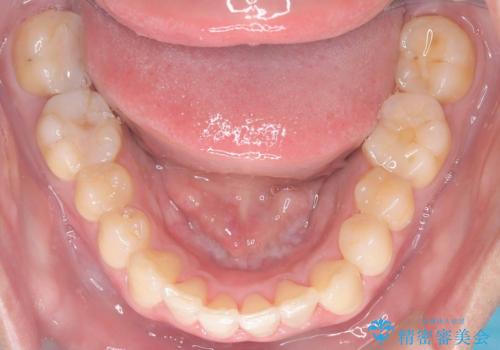

- 「上の前歯の捻じれと下の前歯のでこぼこを治したい」を主訴に来院された患者様です。

矯正検査の結果、非抜歯で矯正可能だったためインビザラインで治療を行いました。

アーチの拡大とIPRで叢生を改善いました。

11ヵ月で矯正を終える事ができ患者様も大変ご満足されていました。